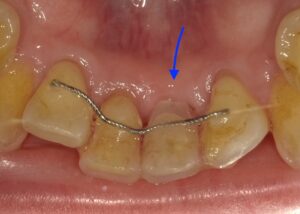

画像は抜けてしまったため入れ歯の歯を接着剤でとめて

います。自然な感じではありますが先ほどの画像ほど

色がマッチしていません。

このように暫間固定は一時的な治療とはいえ、見た目的には

見た目を改善でき患者様にとても喜ばれる治療法になります。

しかし強度的に強くありませんので、硬いものを噛みすぎない

など気をつけないといけません。